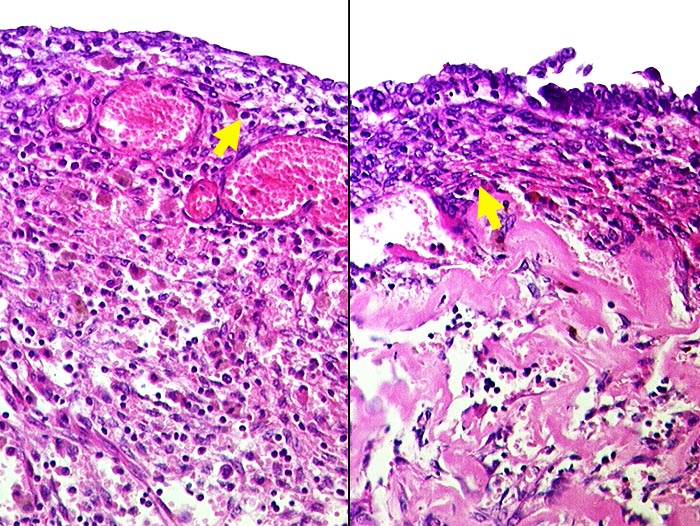

g/ Endometriosezyste des Ovars

Endometriosezyste des Ovars

Ausstriche von Endometriosezysten enthalten Hämosiderin-beladene Makrophagen vor einem Hintergrund hämolytischer Erythrozyten. Die auskleidenden Endometriumzellen sind nur selten im Ausstrich nachweisbar und bilden kleine Aggregate. Meist sind die Epithelien stark degeneriert. Die Kerne sind klein, rund und hyperchromatisch, das Zytoplasma ist fein vakuolisiert. Die zytologische Diagnose kann nur gestellt werden, wenn Endometriumzellen nachweisbar sind. Ansonsten ist der Befund bei entsprechender klinischer Verdachtsdiagnose mit einer Endometriosezyste vereinbar. Differentialdiagnostisch kann es sich aber auch um eine eingeblutete funktionelle Zyste oder einen zystischen Tumor handeln.